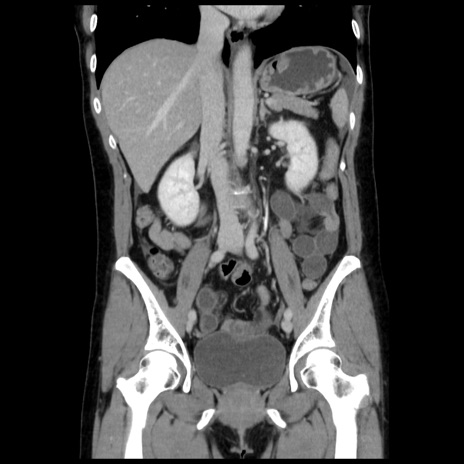

症例10(冠状断像)

【症例】 50歳代女性

【主訴】 腹痛

【現病歴】前日生レバーを食べた。今朝に排便あり。 昼前に突然発症の腹痛を生じ、当院救急外来を受診した。

【既往歴】 子宮筋腫にてで子宮全摘後

【身体所見】 意識清明、腹部:平坦、軟、下腹部やや左を中心に圧痛・反跳痛あり、筋性防御あり

【データ】WBC 7800、CRP 0.07